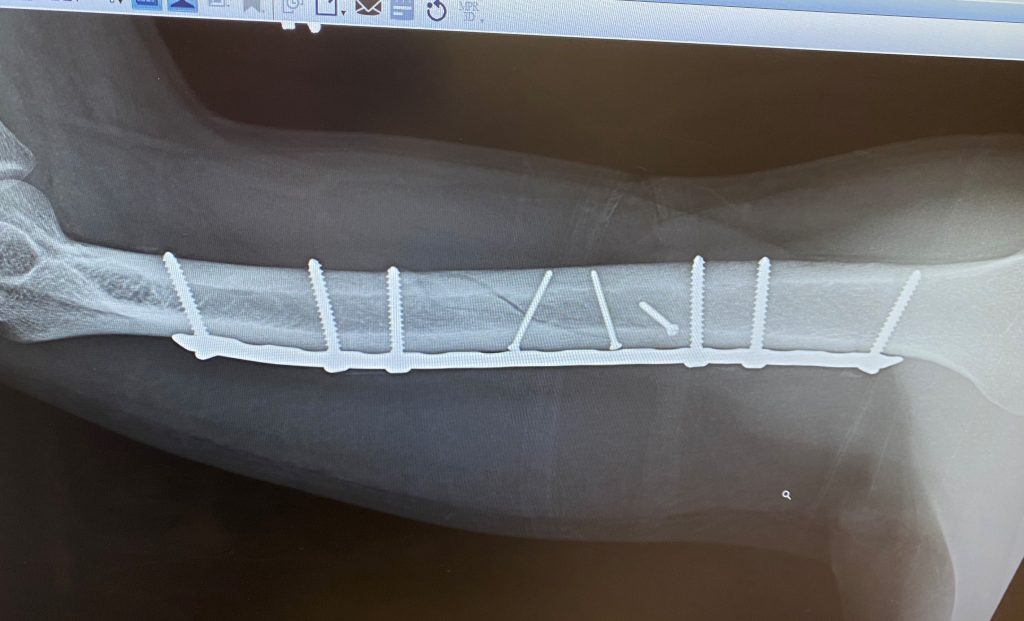

Arm and Elbow Fractures

When Ginny broke her arm in May we were worried that it would put a dampener on her summer fun. After a very successful surgery with Dr. Fabricant and the awesome team at HSS, Ginny kicked off the summer with a cast on that went all the way up to her shoulder. No cast could hold Ginny back though, and within a few weeks of getting it off she was already almost back to 100%.